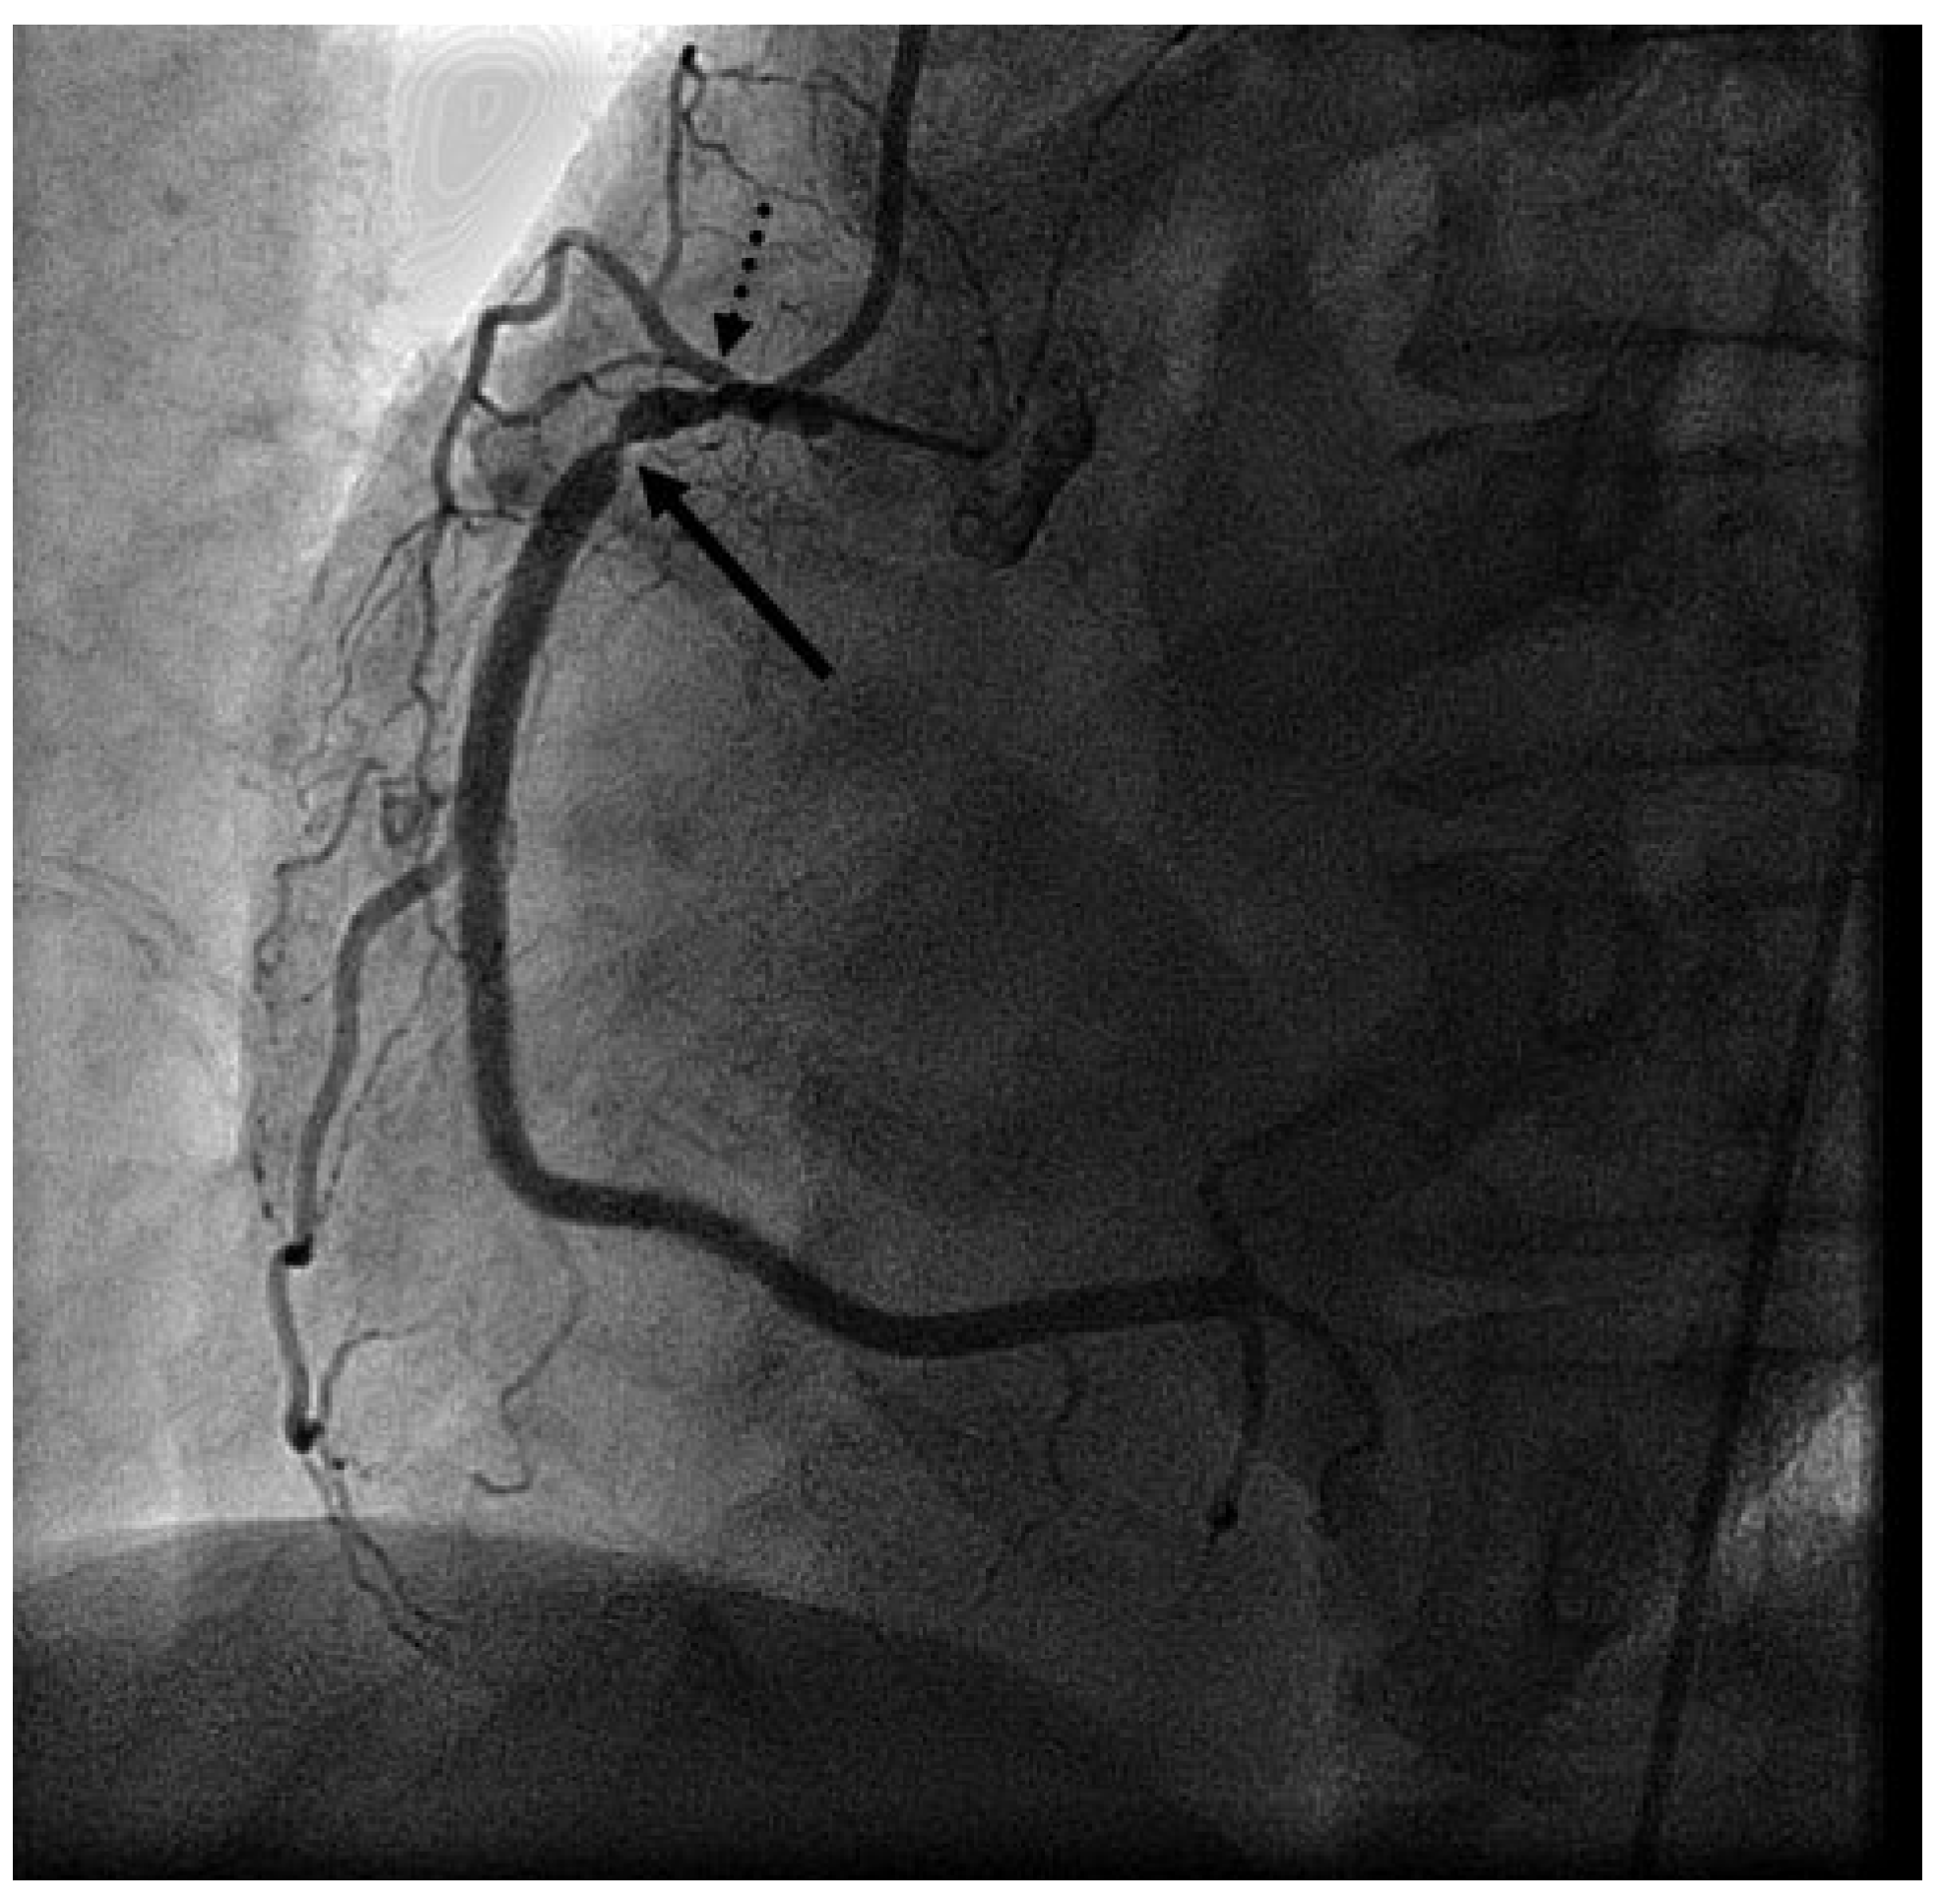

Presenting ECG changes (inferior ST-elevations) and rising cardiac enzymes, the patient was transferred to the acute care hospital and cath lab. Emergency coronary angiography showed severe stenotic lesions in the proximal right coronary artery (RCA) (Figure 1), in the proximal left anterior descending artery and in the diagonal and marginal branches. Due to cardiogenic shock and inferior ECG changes, a percutaneous coronary intervention in the RCA was organised. After engaging the RCA with the guide catheter, total occlusion of the RCA was observed. The coronary wire was immediately placed in the distal RCA but this failed to restore the flow (Figure 2).

Figure 2. LAO view of the RCA: occluded RCA after coronary guidewire placement in the distal artery.